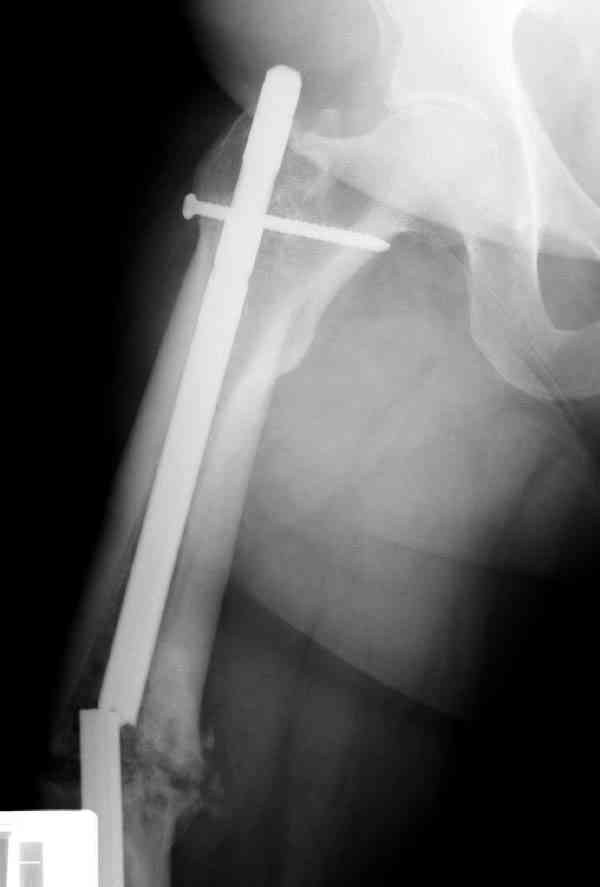

Сросшаяся малоберцовая как распорка привела к образованию ложного сустава. В таких случаях удаляем сломанный штифт и проводим стимуляцию ложного сустава рассверливанием. Рассверливание канала создает стимуляцию на месте ложного сустава, и динамический вариант блокировки штифта с большим диаметром создаст стабильность. Ранняя нагрузка после остеотомии малоберцовой приведет к сращению ложного сустава.

Приспособление для удаления сломанных штифтов и наличие ЭОП облегчит задачу. При отсутствии крючка тогда можно применить обычный длинный ball pointed guide wire от интрамедулярного набора. Проволока, пропущенная за пределы гвоздя и зажатая другая вытащат сломанный конец штифта без проблем.